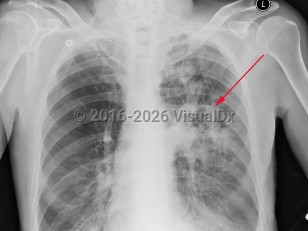

Chest pain, Pleural effusion, 50-59 year old Female

Lung cancerLung cancer

TuberculosisTuberculosis

Lung abscess